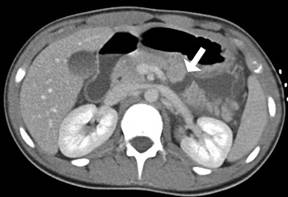

A computed tomography (CT) of the abdomen revealed complete transection of the pancreas at the junction of the body and tail (Figure 1) with associated peripancreatic fluid extending into the lesser sac, flattening the posterior stomach, as well as tracking into the left anterior perirenal space and left colic gutter. A moderate amount of pelvic free fluid was also evident, as well as generalized mild small bowel dilatation. Biliary and pancreatic ducts were normal in size. Duodenal hematoma was excluded; the spleen also appeared normal. CT scans of the cervical, thoracic, and lumbar spine were unremarkable.

Figure 1. CT scan of the abdomen demonstrating complete transection of the pancreas at the junction of the body and tail approximately 24 hours following initial injury. Arrow indicates pancreatic transection. |